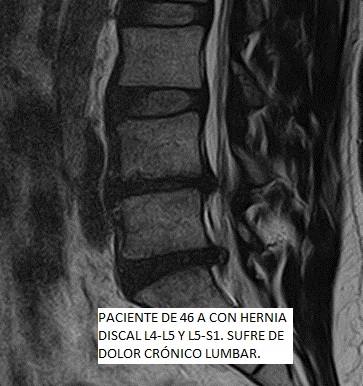

Las patologías del disco intervertebral se consideran de significativa contribución a la sensación dolorosa. Las hernias discales, protusiones discales y la artrosis, son las patologías degenerativas más comunes. La causa más frecuente del DOLOR LUMBAR es la degenerativa, asociada a cambios biomecánicos en la columna vertebral, resultando en un daño que puede alcanzar severa intensidad y provocar una gran limitación de nuestra calidad de vida.

La TERAPIA REGENERATIVA NEUROESPINAL, desarrollada por el equipo de Neurocirugía de la Clínica del Remei (COT- Neurocirugía Remei) y dirigida por la Dra. Ivón González Valcárcel, es una Intervención novedosa y mínimamente invasiva exenta de reacciones adversas, avalada por evidencia científica, que utiliza la biotecnología. Nos brinda beneficios inmediatos en el control del DOLOR LUMBAR, así como ofrece efectividad en revertir la cascada degenerativa, con la consecuente REPARACIÓN y REGENERACIÓN del disco intervertebral y otros tejidos afectados.